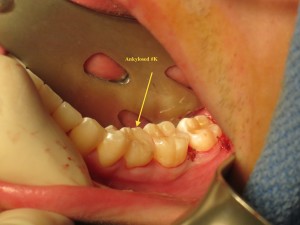

Take a look at this subsequent case. An 18yo that presented to us for extraction of his third molars and a stuck baby tooth #K. We elected to extract all 4 third molars under IV sedation and the same time extracted his baby tooth #K with immediate implant placement and immediate temporary crown….he basically left with a replacement tooth in one hour. Take a look at the sequence:

Preop – Ankylosed or stuck tooth #K Extraction site